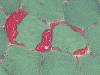

Pathology of the case: On hematoxylin-eosin stained frozen sections, there are many stongly basophilic, irregular subsarcolemmal depositions (Panel A and B). There is no significant variation in fiber diameter, increase in centrally located nucleus, inflammation, necrotic fiber, regenerating fibers or target fibers. These deposits appear bright red on modified Gomori's trichrome (Panel C). On ATPase reaction at pH 4.6 (dark fibers are type 1, pale fibers are type 2a while intermediate-intensity fibers are type 2b), there is no fiber type predominance (Panel D). Although the deposits are not visualized in the ATPase preparation, they are strongly reactive in NADH-TR reaction. Intesestingly, these deposits are not visualized in another preparation of oxidative enzyme- succinate dehydrogenase (Panel F). On the adenylate deaminase preparation, these deposits are strongly reactive (Panel G). The subsarcolemmal deposits are well visualized under the electron microscope which is electron dense (Panel H). On cross sections, these deposits are bundles of densely packed polygonal to round tubules with double walls that are arranged in small fascicles (Panel  I and J). The tubules are about 50-80 nm in diameter. The tubular aggregates also arrange in longitudinal bundles that run along the myofibrils (Panel K).

Tubular aggregates are well demonstrated in many routinely used histochemical stain. In general, tubular aggregates appear as irregular, subsarcolemmal depositions 4. They appear bright red in modified Gomori's trichrome. These aggregates appear strongly basophilic on hematoxylin-eosin stained frozen sections but they are quite indistinctive in paraffin embedded sections stained with hematoxylin-eosin. The aggregates appear intensely dark blue on NADH-TR reactions and this feature lead to the early impression that they are derived from the mitochondria. However, their lack of succinate dehydrogenase. Tubular aggregates are also strongly positive for lactate dehydrogenase and adenylate deaminase. These features argue against a mitochondrial origin.  Tubular aggregates are usually but not invariably found in type II fibers.